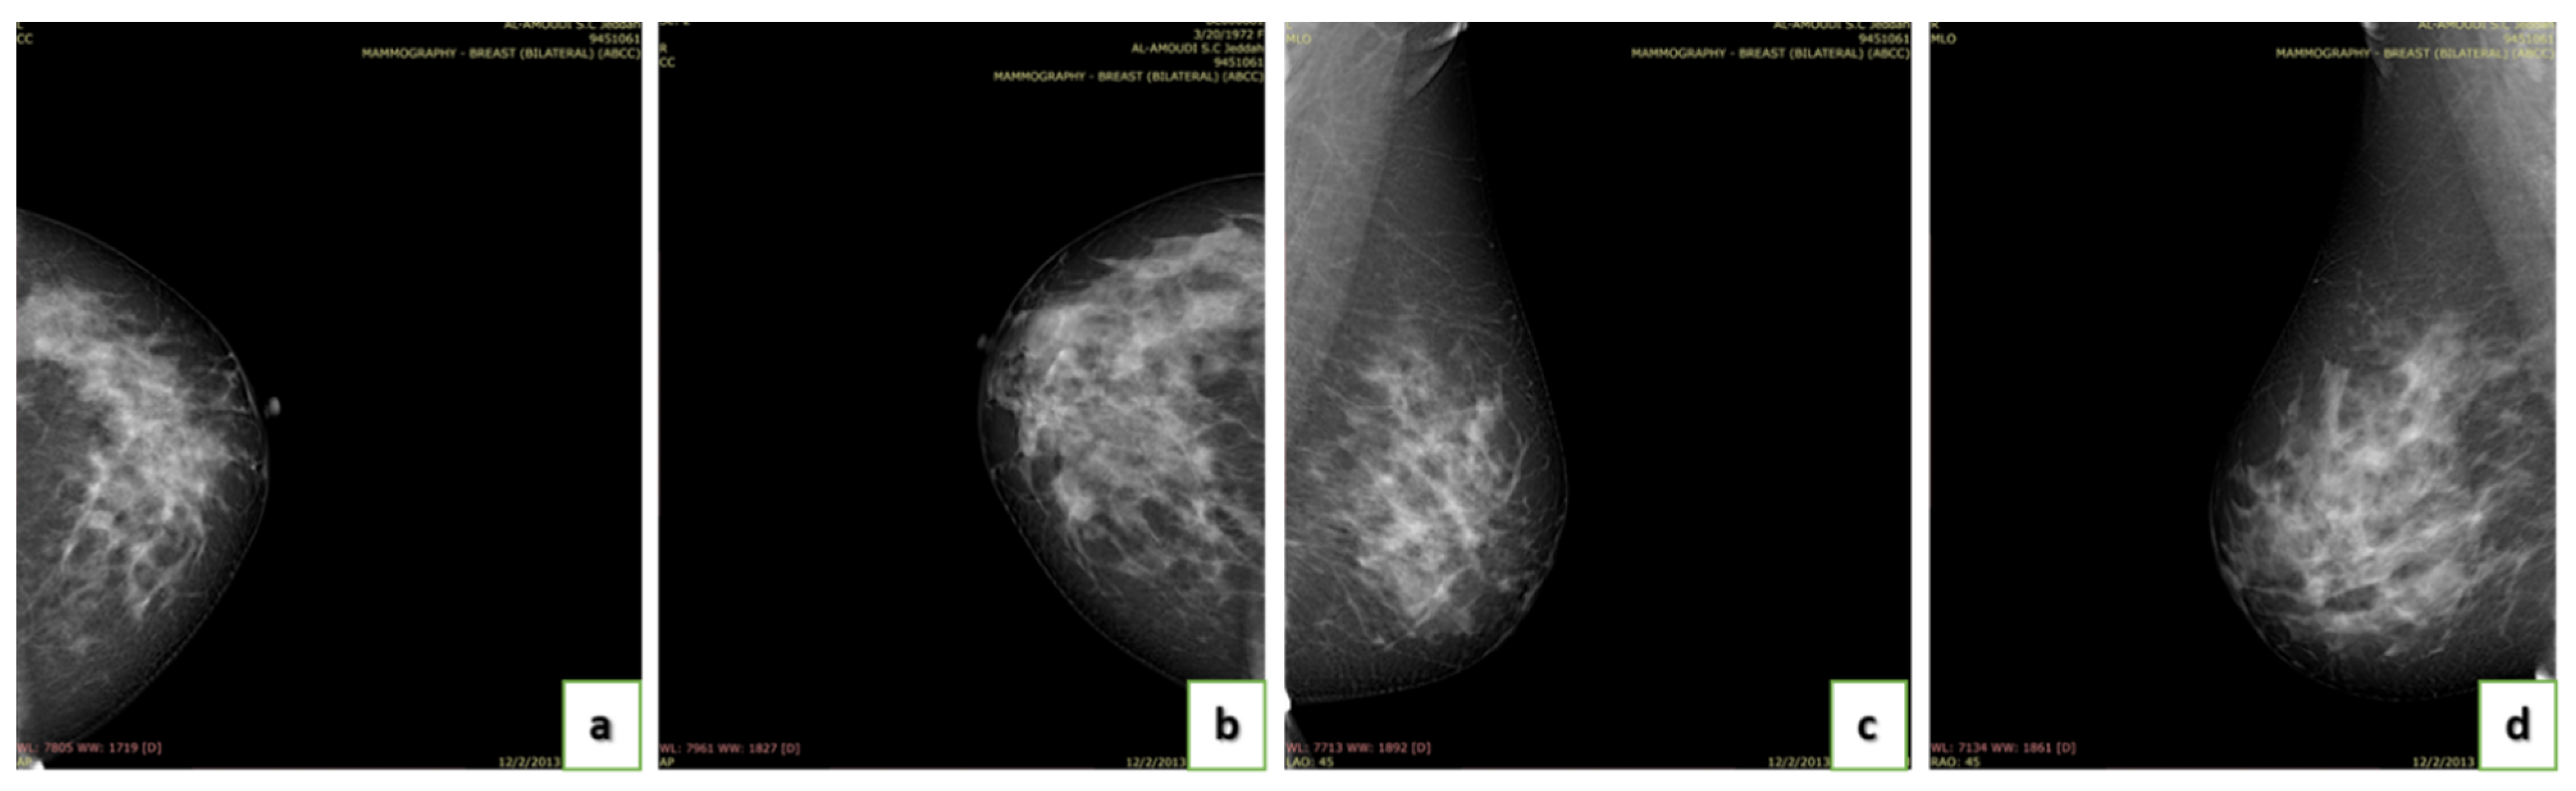

4.3. Data Acquisition

4.4. Breast Density

- A (0–25%): Almost entirely fatty indicates that the breasts are almost entirely composed of fat. One out of ten women has this result.

- B (25–50%): Scattered areas of fibroglandular density indicate some scattered areas of density, but most of the breast tissue is non-dense. Four out of ten women have this result.

- C (50–75%): Heterogeneously dense indicates that there are some areas of non-dense tissue but that most of the breast tissue is dense. Four out of ten women have this result.

- D (75–100%): Extremely dense indicates that nearly all breast tissue is dense. One out of each women has this result.